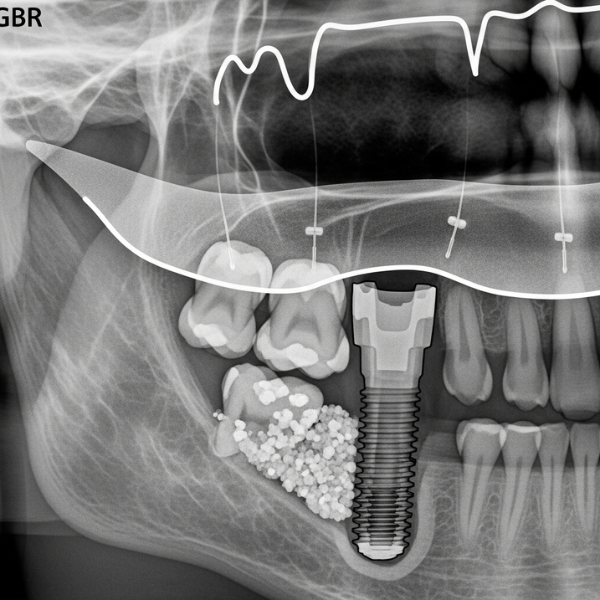

Os procedimentos de regeneração óssea guiada (ROG) utilizam técnicas e biomateriais para estimular o crescimento ósseo em áreas com deficiência óssea. Esses procedimentos envolvem a utilização de enxertos ósseos, membranas e fatores de crescimento para promover a regeneração do tecido ósseo.

A regeneração óssea guiada (ROG) é um procedimento fundamental na implantodontia, visando promover a regeneração óssea em áreas com defeito ósseo. Este procedimento utiliza técnicas e materiais específicos para direcionar o crescimento ósseo, criando um ambiente favorável para a colocação de implantes dentários. A ROG é essencial para pacientes que perderam volume ósseo devido a trauma, extrações dentárias ou reabsorção óssea, permitindo a reabilitação oral e melhorando a qualidade de vida do paciente.

Ambas as técnicas são essenciais para garantir a estabilidade do implante dentário, utilizando enxerto ósseo e biomateriais para orientar o crescimento ósseo.

Na regeneração óssea, uma variedade de materiais desempenha papéis cruciais, cada um com suas características e aplicações específicas. Entre os mais comuns, podemos destacar:

- O enxerto ósseo autógeno, colhido do próprio paciente, reconhecido pela sua alta biocompatibilidade e capacidade de estimular a formação óssea.

- Enxertos ósseos alógenos (de doadores), xenógenos (de origem animal, como o bovino) e sintéticos, que oferecem alternativas viáveis dependendo da situação clínica.

Adicionalmente, as membranas, sejam reabsorvíveis ou não, são essenciais para proteger o enxerto e direcionar o crescimento ósseo, otimizando o processo de regeneração óssea guiada.

Após a reconstrução óssea, o procedimento de colocação de implantes dentários requer planejamento cuidadoso. O cirurgião dentário avalia a área reconstruída para garantir que o osso tenha volume e densidade suficientes para suportar o implante. A instalação do implante dentário é realizada seguindo protocolos precisos para assegurar a osseointegração e a estabilidade a longo prazo, permitindo a reabilitação oral do paciente e melhorando sua qualidade de vida.